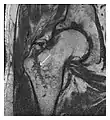

Proximal femoral fractures usually occur in osteoporotic patients, and their signs include subtle neck angulation, trabecular angulation, and subcapital impaction line. A frog-leg lateral view may be helpful if the greater trochanter is short enough. However, positioning can be difficult because of hip pain. In patients with strong suspicion of proximal femoral fracture and negative radiographs, MRI limited to coronal T1 W images and scintigraphy can be highly valuable (Figures 13 and 14). Such an option, with limited examination time, is cost-effective and allows reliable exclusion or confirmation of the diagnosis, preventing an unnecessary stay at the hospital or delayed treatment. Moreover, MRI helps to detect soft tissue abnormalities which are more frequently seen in femoral, acetabular, and pubic injuries than sacral lesions. Concomitant fractures are also frequently seen in typical pelvic sites.[1]

a

b

Figure 14: Subcapital insufficiency fracture in a 55-year-old man with a left hip pain without a history of trauma. Anteroposterior and Lauenstein view radiographs centered on the left hip do not show an obvious fracture line, but mild acetabular osteophytosis was noted consistent with hip osteoarthritis (not shown). (a) Coronal T1-weighted MRI shows a linear low-signal band through the femoral neck corresponding to a fracture line (arrowheads). (b) Bone scintigraphy shows focal uptake (arrow) corresponding to the fracture.[1]